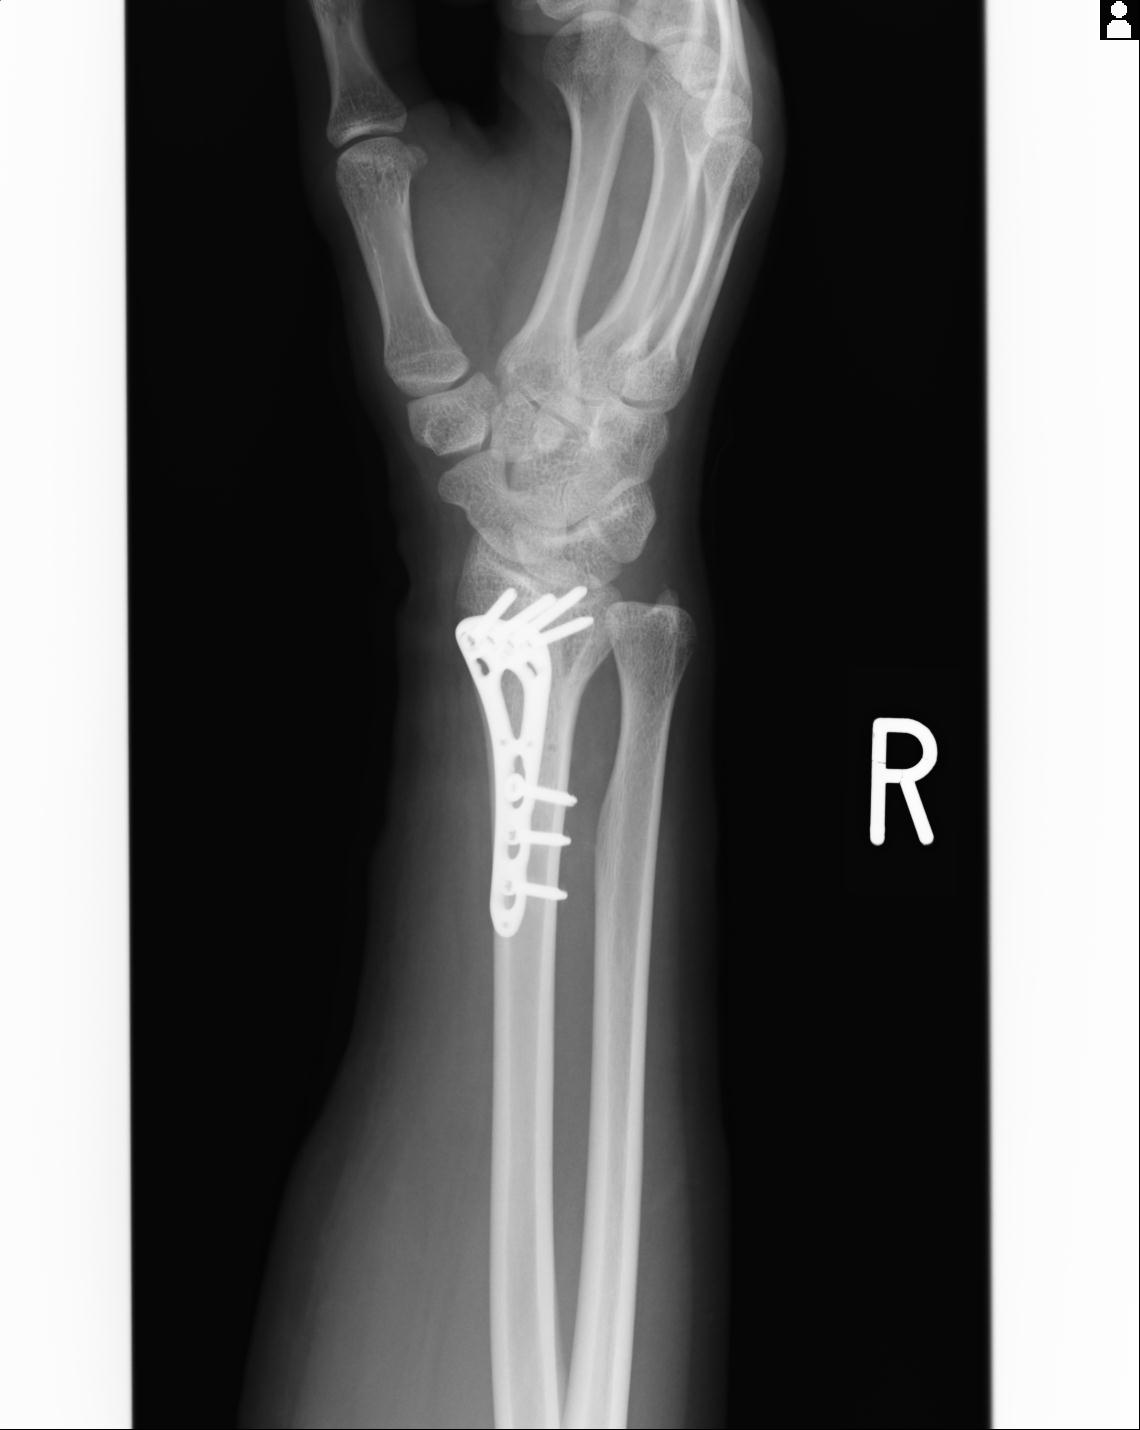

102766 1/5 1/12 左手関節 4R 28歳男性 左橈骨遠位端